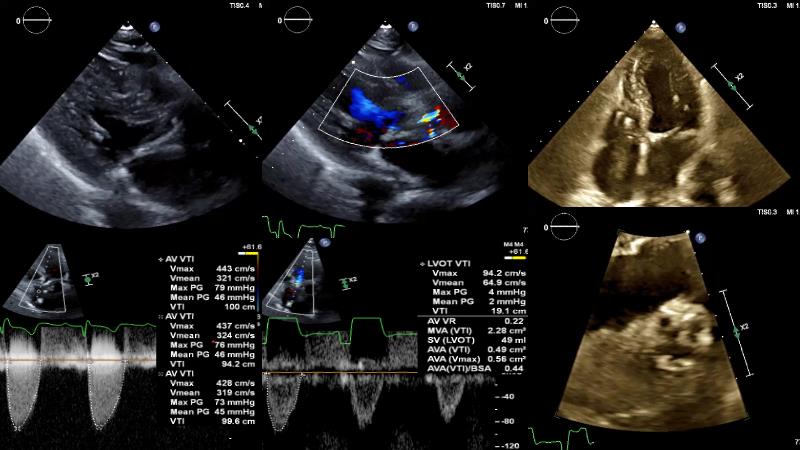

The primary focus of this GulfPCR-GIM 2023 session revolves around pre-procedural planning considerations, valve selection, and managing complex anatomies using both traditional self-expanding valves and the Evolut FX system. Additionally, the session aims to explore the work-up protocol for patients grappling with severe AS and advanced CKD, elucidate the algorithm for selecting the appropriate TAVR platform, discuss strategies to reduce contrast utilization, and highlight the distinctive advantages offered by the Evolut FX system.

• To discuss challenges in TAVI procedural planning

• To discuss valve choice in challenging anatomies